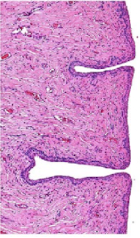

What organ is in the image provided and what phase of the estrous cycle is it in?

vagina in diestrus